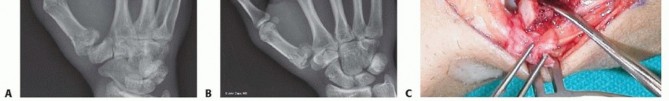

Our imaging protocol must be exhaustive to provide a three-dimensional understanding of the fracture morphology. Standard hand radiographs are insufficient due to the unique 30-degree pronated position of the thumb relative to the rest of the carpus. A True AP View of the Thumb CMC Joint (Robert's view) is obtained with maximal forearm pronation, placing the dorsum of the thumb flat on the cassette. This optimizes visualization of the joint space and the critical ulnar fragment. The True Lateral View (Billing and Gedda) is achieved with the hand pronated 20 degrees and the thumb flat on the cassette, with the X-ray beam tilted 10 degrees from vertical in a distal-to-proximal direction.

For complex, multi-fragmentary Rolando fractures, a Traction View under fluoroscopy is indispensable. Distraction at the CMC joint utilizes ligamentotaxis to help delineate comminuted fragments and assess the potential for closed reduction and percutaneous pinning versus the absolute need for open plating. Furthermore, when plain films inadequately delineate the spatial orientation of fracture fragments, particularly in Zone 2, a high-resolution Computed Tomography (CT) scan is strictly indicated. 3D reconstructions are invaluable for preoperative templating, allowing the surgeon to precisely map screw trajectories and select appropriate plate morphology before entering the operating theater.

Open Reduction and Internal Fixation (ORIF) - Wagner Approach

For fractures with large volar-ulnar fragments (>20% of the articular surface), displaced Rolando fractures, or cases where closed reduction fails, ORIF is unequivocally mandated. The classic Wagner approach provides unparalleled exposure to the thumb CMC joint. A curvilinear incision is made along the glabrous border of the thenar eminence, curving dorsally at the level of the CMC joint.

Meticulous superficial dissection is required to identify and protect the sensory branches of the superficial radial nerve dorsally and the palmar cutaneous branch of the median nerve volarly. The thenar musculature (abductor pollicis brevis and opponens pollicis) is sharply elevated from the metacarpal shaft and retracted volarly. The joint capsule is then incised longitudinally or in an L-shaped fashion to expose the articular surface. The hematoma is evacuated, and the fracture fragments are meticulously debrided of interposed soft tissue.

For a large fragment Bennett fracture, the shaft is reduced to the volar-ulnar fragment using a pointed reduction clamp. Provisional fixation is achieved with a K-wire. A 1.5mm or 2.0mm lag screw is then placed perpendicular to the fracture plane. The near cortex must be overdrilled (gliding hole) and the far cortex underdrilled (thread hole) to achieve true interfragmentary compression. The screw head should be countersunk to prevent hardware prominence beneath the thenar muscles.